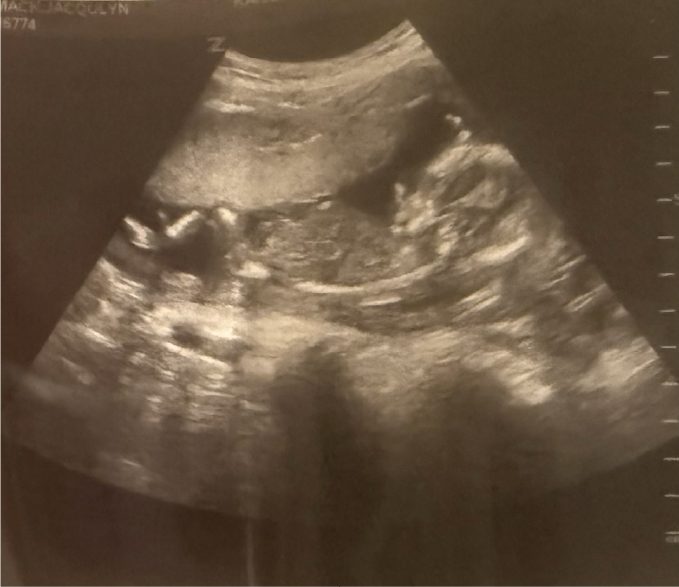

As we finished the conversation, one of the directors asked if we had any plans to have more children. My wife and I immediately shared one of those looks—you know, the kind where words become irrelevant. We wanted one more, but between everything going on in the church and all the complications that Jacqulyn had had with past pregnancies, well, now just was not the right time. So we turned and, with much confidence, responded, “Maybe in a few years, but we aren’t even thinking about it right now.” Of course, there was just one problem . . . Jacqulyn was already expecting; we just didn’t know it yet. So, with a smile spreading across my face as I type these words, I can confidently say that God’s ways are not always our ways, but they sure are so much better than anything we can imagine, and we are excited to meet one more member of the family, Alyssa Kate McCormack, come December.

With this little addition, our plans for this year have just become very fluid, so I would ask you to be praying with us for wisdom. Due to Jacqulyn’s complicated pregnancy history, she will be returning to the States as she enters the beginning of her third trimester at the end of August. However, in the midst of this, we are also having to renew our Peruvian residency once more, and during this process, she is not allowed to leave the country. So please be praying with us that this process will go smoothly